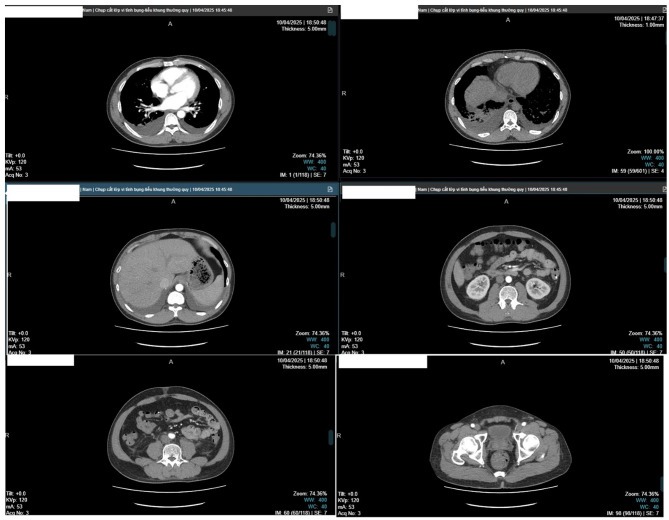

Case presentation: A 42-year-old Vietnamese man developed abdominal distension, facial edema, and dyspnea after initiation of Helicobacter pylori eradication therapy. Imaging revealed pleural, pericardial, and peritoneal effusions, periportal edema, and interstitial pulmonary edema. Laboratory results showed hyponatremia, hypoalbuminemia, and mild anemia. Autoimmune screening revealed ANA positivity (1:80, speckled) and lupus anticoagulant, though extractable nuclear antigens were negative. The patient improved rapidly with corticosteroids and antihistamines.